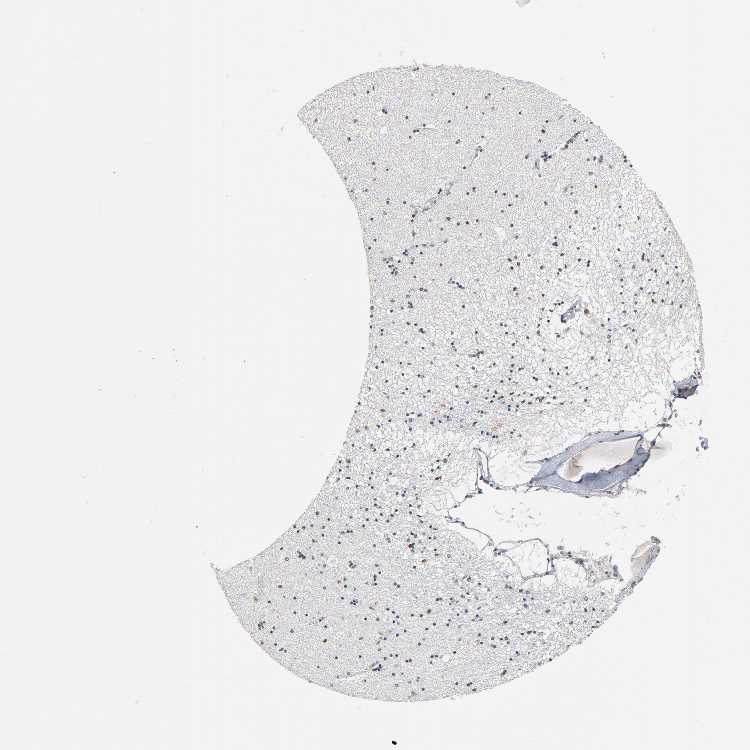

HIPPOCAMPUS - Antibody stainingi

Antibody staining in the annotated cell types in the current human tissue is reported as not detected, low, medium, or high, based on conventional immunohistochemistry profiling in selected tissues. This score is based on the combination of the staining intensity and fraction of stained cells.

Each image is clickable and will lead to virtual microscopy that enables deeper exploration of all samples and also displays staining intensity scores, fraction scores and subcellular localization as well as patient and tissue information for each sample.

Antibody HPA004345

Glial cells Low

Neuronal cells High